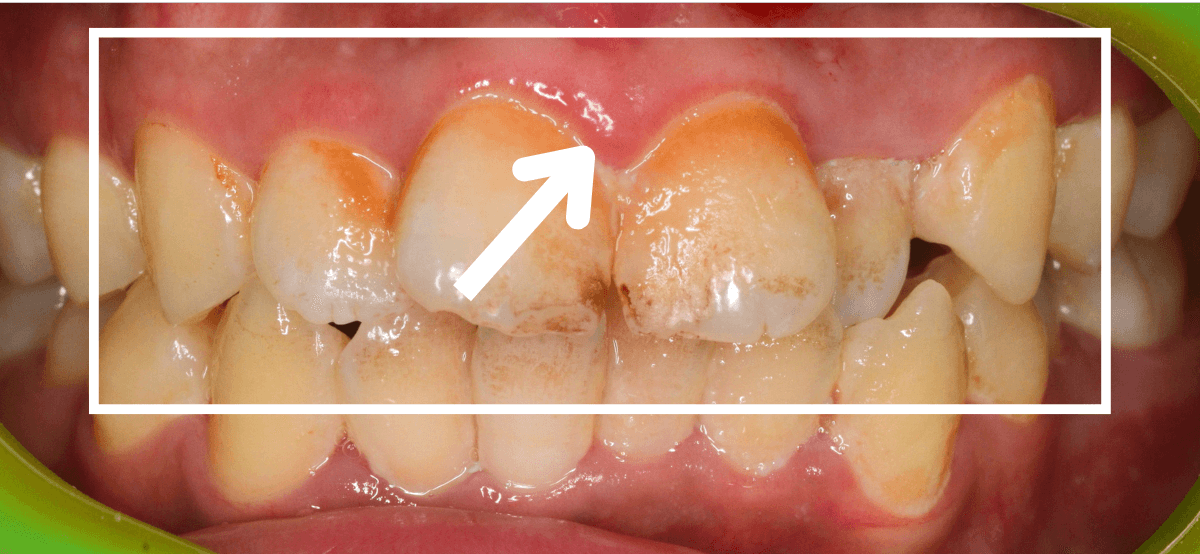

Case.2

今回は、上の前歯の縁下歯石の除去をしたお話です。

写真の左の矢印の歯肉が退縮して腫れています。

右の矢印の歯肉と比べてみるとわかると思います。

こういった歯肉の形をしている部分は、歯石がたまっていることが多いです。

拡大してみると、縁下歯石(歯肉の中に入り込んだ歯石:歯肉に大きく悪影響を与えます)が顔を出しているのがわかります。

かなり歯肉の中に歯石が入り込んでしまっていると思われます。

歯肉の中の歯石は歯にべっとりとこびりつきますので、除去するには麻酔をして引きはがす処置が必要です。